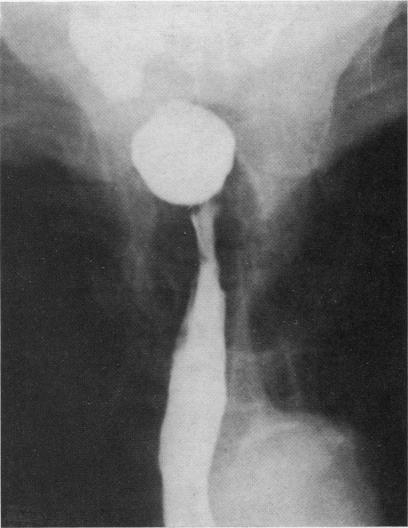

The anatomical variations of the Plummer-Vinson stricture in the cervical oesophagus. An X-ray atlas.

Ulster Med J. 1978;47 Suppl 2(Suppl 2):15-59.